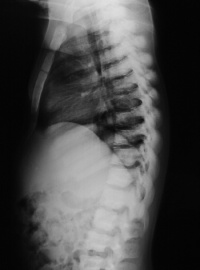

脊柱脊柱后凸或侧弯畸形骨盆畸形。

①X线:钙化带模糊,干骺端增宽,边缘呈毛刷状或杯口状改变。

肾性佝偻病x线表现

(二)临床分期 本病的发生发展是一个连续过程。依据年龄、病史、症状、体征、X线及血生化等项综合资料可分为活动期(初期、激期)、恢复期和后遗症。无条件作X线及血生化检查者,可只根据临床资料进行分析。

2、激期:常见于3个月至2岁的小儿。有明显的夜惊、多汗、烦躁不安等症状。同时可有中度的骨骺改变体征。X线片可见临时钙化带模糊消失,干骺端增宽,边缘不整呈云絮状,毛刷状或杯口状,骨骺软骨加宽。血钙、血磷均降低,硷性磷酸酶增高。